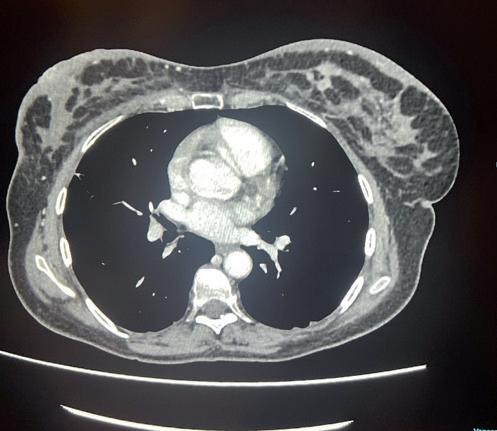

La TC total body con mdc effettuata per stadiazione oncologica, evidenzia fegato pressoché sostituito da lesioni ipodense tendenti alla confluenza di significato secondario, con multiple focali alterazioni della struttura ossea a carico del bacino, vertebre toraciche e lombari, sterno e coste.

La prima rivalutazione strumentale effettuata a Settembre 2023 con TC, dopo 4 cicli di trattamento, registra una risposta iniziale in sede epatica, una completa normalizzazione degli indici di funzionalità epatica così come dei marcatori tumorali e una stabilità strumentale della formazione mammaria e ascellare. Quindi, incoraggiati da un quadro clinico-laboratoristico drasticamente migliorato, si aggiunge paclitaxel 80 mg/m2 q7 al trattamento anti-HER2, sulla scorta dei dati dello studio di fase IIIB PERUSE.

Tuttavia, nonostante la buona risposta iniziale, la TC total body con mezzo di contrasto del 28/12/2023 (figura 1) evidenzia progressione epatica ed encefalica con un quadro radiologico che mostra sovvertimento encefalico diffuso caratterizzato da numerose lesioni secondarie (almeno 10) a netta impregnazione contrastografica a sede sia cerebrale che cerebellare, prevalentemente subcentimetriche, la maggiore di 13 mm in nucleo-capsulare sx con nucleo necrotico e modesto alone edemigeno perilesionale.